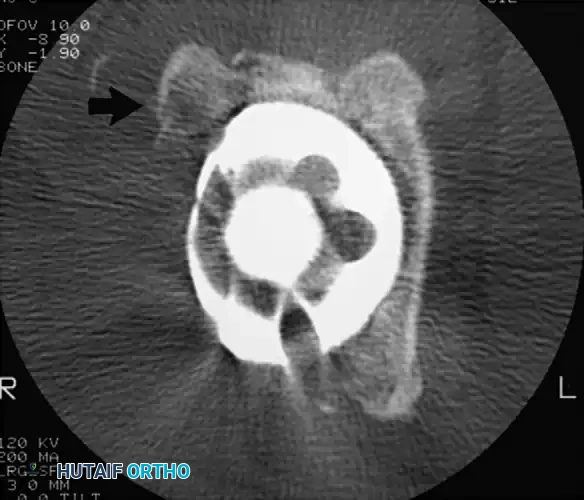

Associated Surgical & Radiographic Imaging